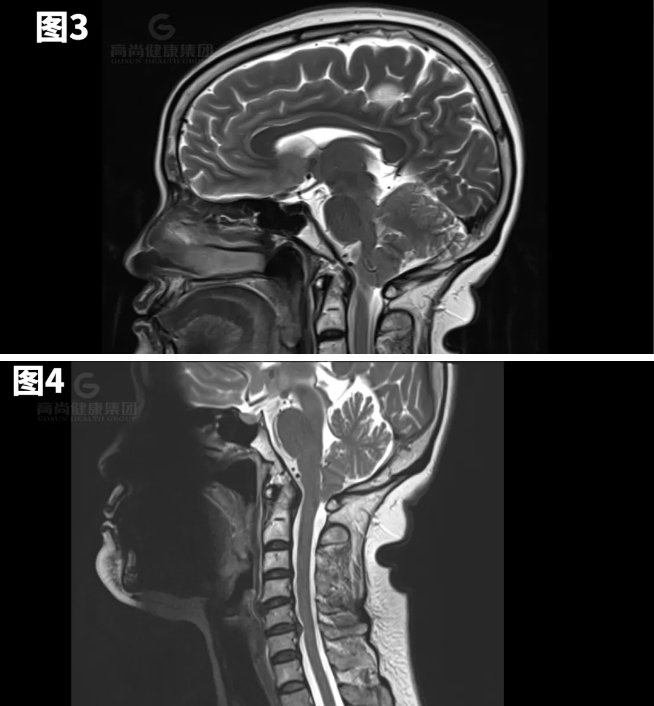

图1-7示小脑扁桃体向下疝出约8mm。

矢状位:扁桃体延伸到枕骨大孔下方,脑干压迫斜坡。

横断位:移位的扁桃体导致周围脑脊液闭塞、髓质前移以及脊髓动脉和椎动脉受压。